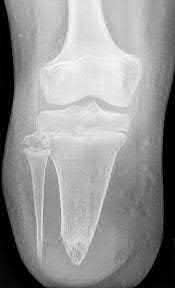

A 25-year-old female is involved in a motor vehicle collision. She presents with the isolated injury seen in Figures A through D. Her leg is swollen but her skin is intact. She has no clinical signs of compartment syndrome. Which of the following treatment options will allow for maintenance of fracture alignment and minimize the risk of soft tissue complications?

The patient presents with a closed distal third metaphyseal-diaphyseal distal tibia fracture with simple intra-articular extension. Immediate intramedullary nailing along with percutaneous fixation of the articular component provides appropriate restoration of length, rotation and alignment and minimizes the risk of wound complication.

Displaced distal third tibia fractures may be associated with simple intraarticular extension. Operative treatment of intra-articular distal tibia fractures has historically been performed with open reduction and internal fixation. Early open reduction and plate fixation of pilon fractures has been associated with high rates of infection and wound complication. In select patterns with simple articular extension, percutaneous screw fixation and medullary nailing may provide appropriate reduction with minimal soft-tissue risk.

Figures A and B demonstrate a distal third tibial shaft fracture with simple intra-articular extension. The axial and coronal CT cuts in Figures C and D further clarify the articular injury. Illustrations A and B demonstrate a comminuted distal third tibial fracture with simple intra-articular extension. Illustrations C and D are fluoroscopic images of the same injury after intramedullary nailing and percutaneous fixation of the articular component.